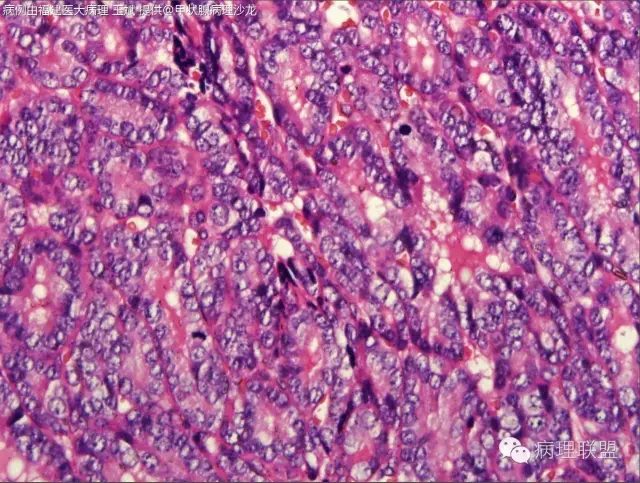

核的特征不明确,是不是得考虑滤泡癌。

滤泡癌和滤泡亚型PTC预后及治疗有何区别?韩帅,我觉得核的特征还是有的@河南新密人医病理科韩峰楼

有少量核沟,如果核够就是滤泡亚型ptc

此片中所显示的“核特征”为人工现象,滤泡癌。

2016版头颈有推荐,PTC中CD56减少或缺失。我最近在摸索,还可以。在年会会场,资料不在手头。但觉道教授新近分类中提倡不去分PTC和FTC,统一采用高中分化。

如果严格按照WHO分类的定义,符合经典乳头状癌和滤泡癌的病例不多,大多数高分化癌病例的组织学病变处于经典乳头状癌和经典滤泡癌,这两个极型之间的位置。